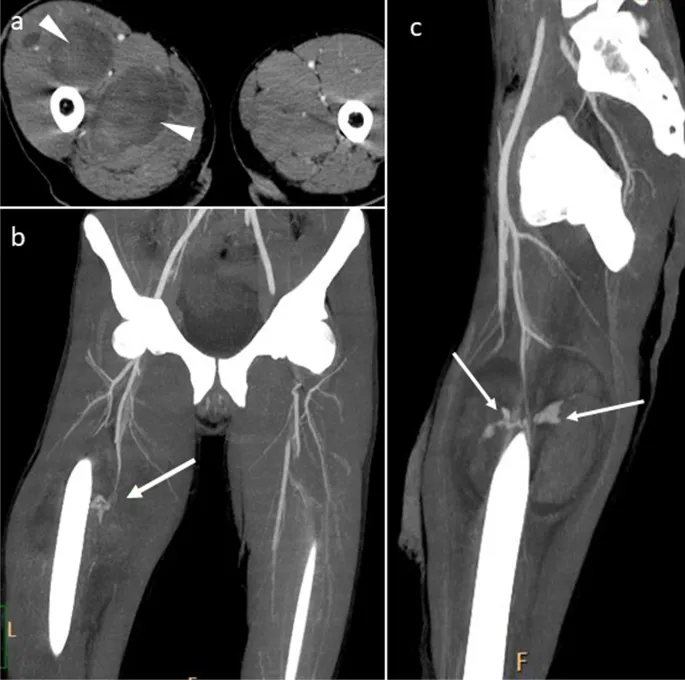

- CT Angiography (CTA): The gold standard for hemodynamically stable patients. It's fast, widely available, and accurately identifies the injury (e.g., transection, pseudoaneurysm).

- Late: Pseudoaneurysm, Arteriovenous Fistula (AVF)